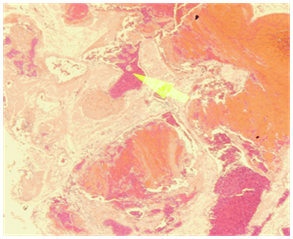

Figure 1 Coronal CT scan showing a large expansile lesion occupying mainly the left maxillary antrum with distended and thinned out bony wall of the left maxillary cavity, the lesion extends to the left nasal cavity and ethmoidal air cells with partial obliteration of the left nasal cavity.